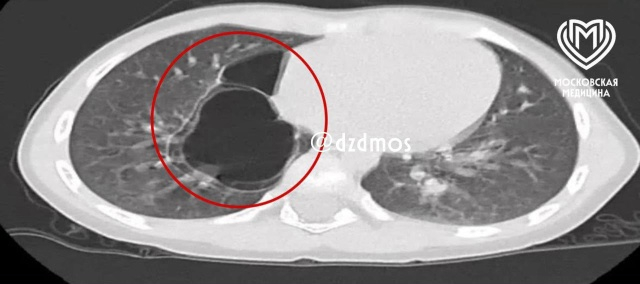

«По словам мамы, малышка часто болела ОРВИ и бронхитами. На рентгенографии медики визуализировали уплотнения в правом лёгком, и для уточнения диагноза провели компьютерную томографию, которая показала врождённый порок развития — кистозно-аденоматозную мальформацию лёгких», — рассказали в больнице.

«Во время операции маленькой пациентке сделали торакоскопию. То есть через небольшой разрез в грудной клетке вошли в плевральную полость и с помощью специального мешка извлекли два разнокалиберных тонкостенных кистовидных образования, размером до 6 см и до 3 см, в которых находилось ещё мелкие кисты», — объяснила  Ампар Фатима, детский хирург хирургического отделения №2.